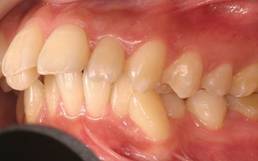

上顎前突+叢生 抜歯矯正(治療期間1年)

治療前、特に上の歯並びに問題がありました

奥歯のかみ合わせもよくありません

口元が突出しています

治療後、正中線も揃いました

小臼歯を抜歯しました

きちんと噛んでいます

大変きれいな横顔になりました。もともと明眸でしたので、矯正治療で明眸皓歯になりました。

笑顔もチャーミング